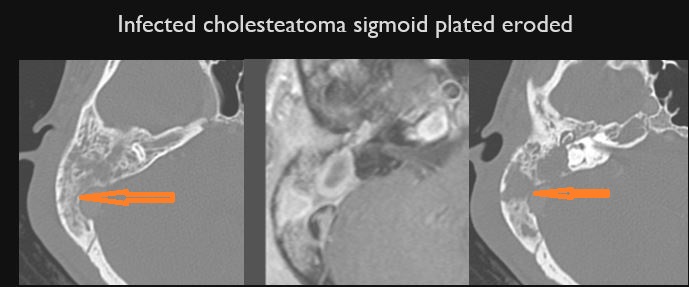

The sigmoid plate of the mastoid is eroded. [Yes/No]

There are dural reactive changes or a subperiosteal/epidural abscess along the sigmoid plate of the mastoid displacing the adjacent sigmoid sinus. [Yes/No]